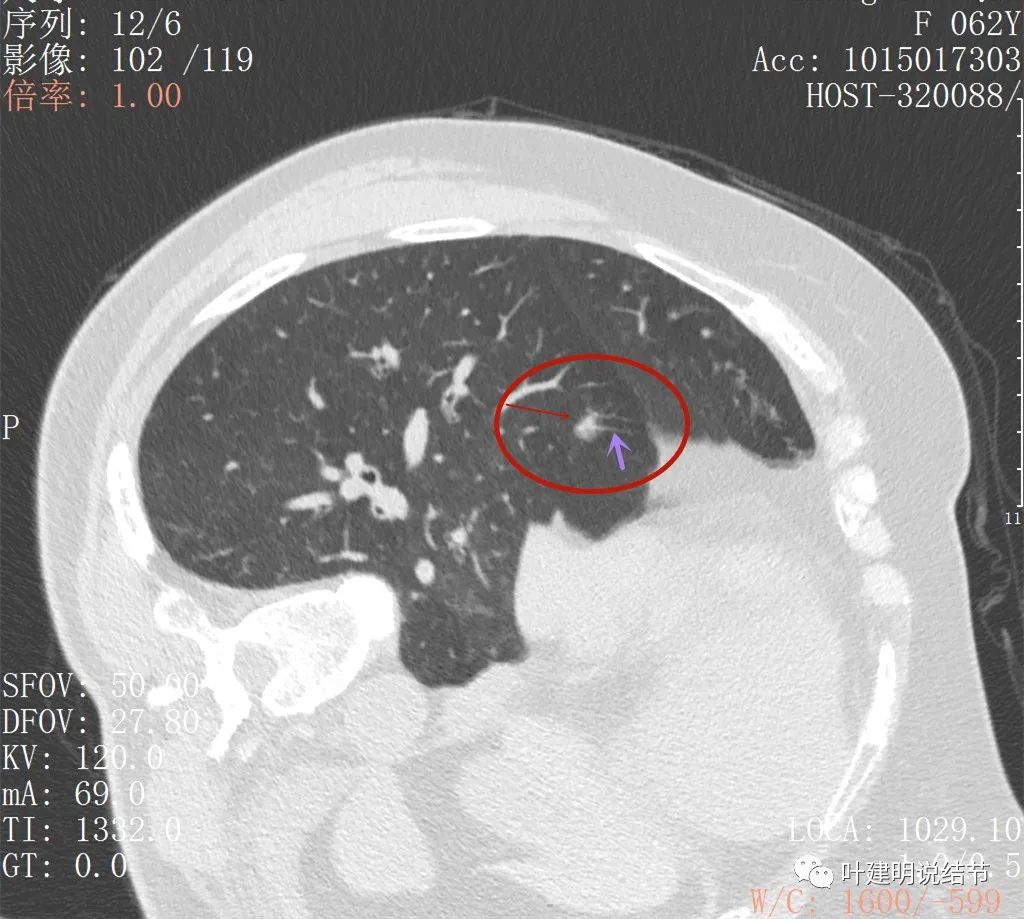

病灶似有毛刺,部分偏长

病灶有毛刺或牵拉的样子,也有少许磨玻璃密度(在边缘部位)